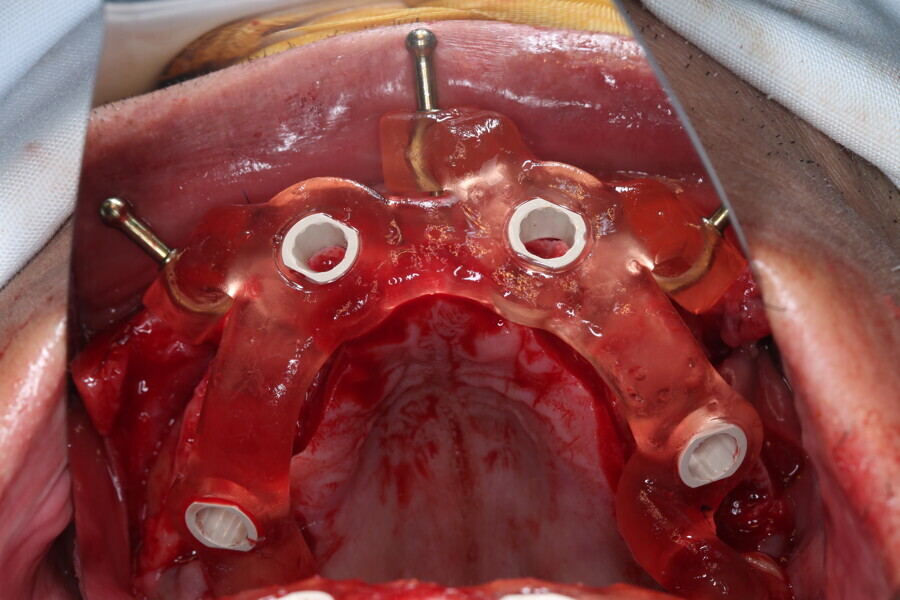

Compromised maxillary dentition treated with Straumann Pro Arch and a digital workflow